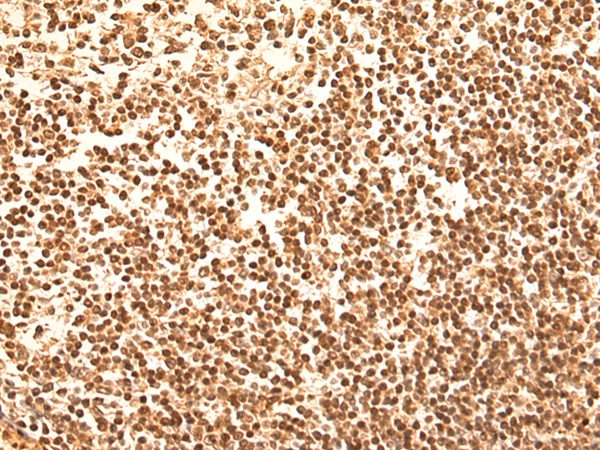

分类: 科研抗体货号: P10589别名: CAN19; S100L应用: WB,IHC反应种属: Human